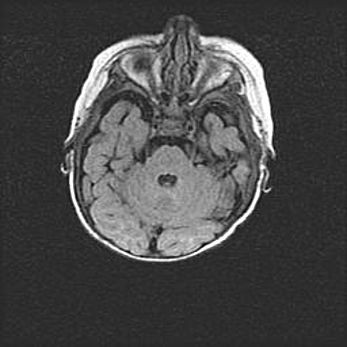

Открытая гидроцефалия.

Возраст: 6 месяцев 15 дней

Вес: 6200 г

Пол: женский

Окружность головы: 41 см

Срок гестации: 38 недель

Гидроцефалия головного мозга у новорожденных – это скопление избыточного количества цереброспинальной жидкости в головном мозге. Ее избыточное скопление в мозге приводит к патологическому расширению желудочков мозга (четырех полостей, расположенных в глубине белого вещества мозга, заполненных цереброспинальной жидкостью и связанных узкими проходами).

Открытый тип гидроцефалии (сообщающаяся) наблюдается тогда, когда нарушен механизм всасывания ликвора в системный кровоток. При этом типе причиной заболевания чаще всего является перенесенные ранее инфекции (например: менингит),  либо же наличие крови в субарахноидальном пространстве.